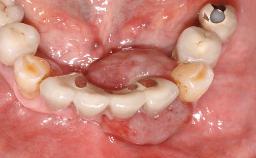

A 66-year-old patient presented because of retention loss of the tooth-supported FDP in the right maxilla (x-13-x-11). The mandibular full-arch implant-supported reconstruction (x-i34-i33-x-x-x-x-i43-i44-x) had suffered extreme wear. His medical history revealed high blood pressure, controlled with anti-hypertensive medication. The patient was a light smoker (2 to 3 cigarettes per day). The existing reconstructions had been performed alio loco about five years previously. That treatment had taken an extensive amount of time, and as early as during the fabrication of the reconstructions, multiple complications had occurred with the provisionals.